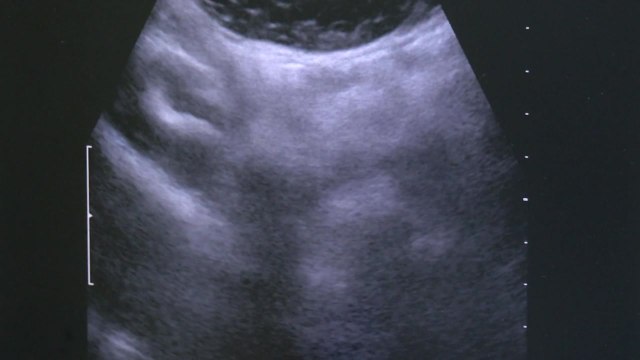

끊임없이 밀려오는 불안은 사람을 힘들게 하고 삶의 질을 떨어뜨리지만, 의학적으로 정확한 원인을 찾지 못해 뚜렷한 해소방안이 없었죠. 그런데 국내 연구진이 뇌세포의 일종인 성상교세포가 불안 행동을 조절한다는 점을 처음 규명해, 불안장애 극복을 위한 새 가능성을 마련했습니다. 이성규 기자가 취재했습니다. [기자] 높이 30cm, 폭 5cm의 십자형 미로입니다. 이 공간에 실험 쥐를 넣자 불안함을 느껴 움츠리며 잘 움직이지 않습니다. 이번에는 머리에 광케이블을 연결한 실험 쥐를 넣고 5분간 파란색 빛을 쪼여 줬습니다 1~2분 정도 지나자 쥐가 돌아다니기 시작합니다. 쥐가 불안감을 이겨낸 건 빛으로 뇌의 특정 세포를 자극했기 때문입니다 앞서 연구진은 쥐의 두개골 속에 가느다란 광케이블 일부를 심었습니다. 광케이블로 쥐의 뇌 속에 파란색의 빛을 직접 쪼여 줍니다. 그러면 불안감에 관여하는 뇌의 특정 세포가 자극을 받게 됩니다. 그동안 불안장애는 주로 뇌의 신경세포를 중심으로 연구됐는데, 연구진은 또 다른 뇌세포인 성상교세포에서 실마리를 찾아냈습니다. [조우현 : 서울대 치의학대학원 연구교수(논문 제1저자) : 빛으로 해마의 성상교세포가 자극받으면 해마 성상교세포에서 ATP의 농도를 증가시킵니다. 그러면 그 근처에 있는 다른 신경세포들이 활성화돼 결국엔 생쥐의 불안감을 감소시킵니다.] 불안장애는 전 세계 성인의 약 30% 이상이 언제든지 경험할 수 있는 질환이지만, 아직 뚜렷한 치료제는 없습니다. 이번 연구는 불안장애의 원인을 새롭게 규명한 것으로, 앞으로 치료제 개발의 단서를 제공했다는 데 의의가 있습니다. [이성중 / 서울대 치의학대학원 교수 : 저희 연구는 신경계에서 해마라는 영역의 성상교세포가 주변에 있는 신경세포를 조절해서 불안증을 조절할 수 있다, 즉 항불안 역할을 할 수 있다. 그래서 불안을 조절하는 새로운 뇌의 세포를 발견했다는 점에서 의의가 있습니다.] 이번 연구결과는 국제학술지 '네이처 커뮤니케이션'에 실렸습니다. YTN 사이언스 이성규입니다. YTN 이성규 ([email protected]) ※ '당신의 제보가 뉴스가 됩니다' [카카오톡] YTN 검색해 채널 추가 [전화] 02-398-8585 [메일] [email protected] ▶ 기사 원문 : ytn.co.kr/_ln/0105_202211072325131954 ▶ 제보 안내 : goo.gl/gEvsAL, 모바일앱, [email protected], #2424 ▣ YTN 데일리모션 채널 구독 : goo.gl/oXJWJs [ 한국 뉴스 채널 와이티엔 / Korea News Channel YTN ] Рекомендуем 불안장애 새 발병 원인 규명...치료제 개발 단초 / YTN посмотреть онлайн видео бесплатно и без регистрации!